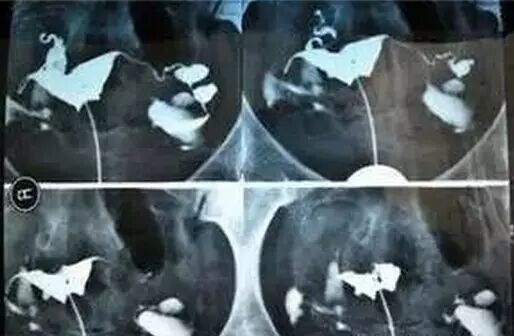

检查:依靠造影检查输卵管  安全高效副作用小

“在导致输卵管堵塞或通而不畅的原因中,80%左右与炎症有关。”庄主任说,她接诊过一位35岁的盆腔炎患者,生育过一个小孩,二胎政策放宽以来,一直想再要个,可是一直没有怀上。她给这位患者做了孕前筛查,发现患者的子宫和卵巢均没有问题。考虑到盆腔炎症随着婚后生活时间的增长,发病率会增高,于是庄主任又建议这位患者做了输卵管造影,结果显示她的输卵管有慢性炎症。